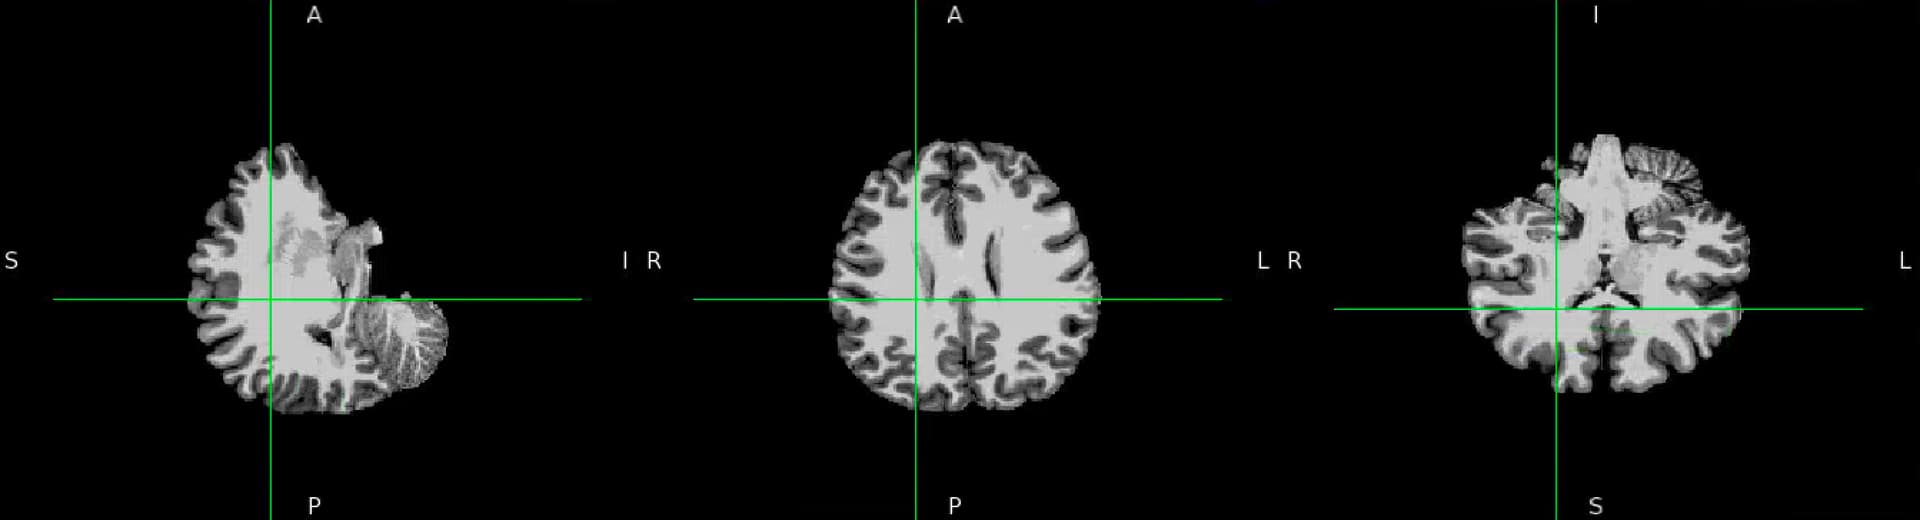

We’ve encountered a problem of misalignment between EPI and T1W. The Freesurfer bbregister failed to align EPI and T1w as well as Freesurfer mri_coreg. While the recon output seems to be alright in the fmriprep output report but it’s in a different orientation when being viewed in fsleyes. Can you kindly provide any suggestions?